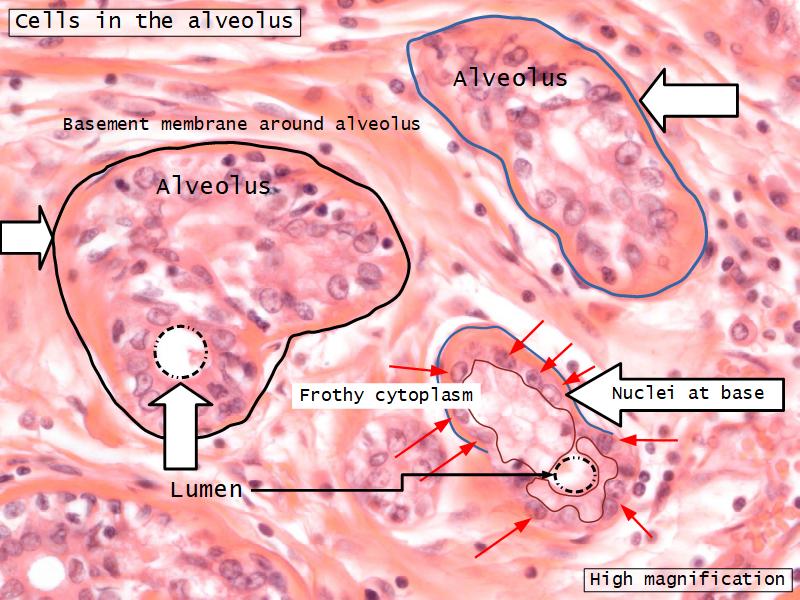

Q06: Epithelium

- Is bordered by a ______.

- Rests on a ______.

Q06: Epithelium

- Is bordered by a lumen.

- Rests on a basement membrane.

Structures

List the structures and cells found in the mammary gland.

Structures

- Lactiferous sinuses

- Stratified squamous near opening on skin

- Stratified cuboidal other parts

- Lactiferous ducts

- Stratified cuboidal

- Myoepithelial cells

- Underlie lactiferous ducts in most areas

- Basal lamina

- Separate epithelial components from stroma

Active gland

- Much larger than resting phase

- Terminal ducts proliferate to form alveoli

- Alveoli

- Surrounded by incomplete myoepithelial cells

Alveolar cells

- Apocrine secretion

- Active state

- Resting state